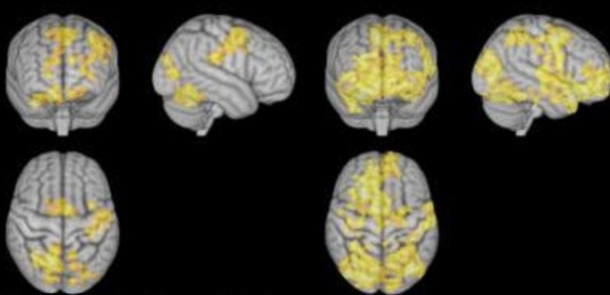

연구진은 일정 실험 참가자들을 대상으로 그들이 ‘비지시적 자발적 명상’을 수행하도록 유도했고 그 동안 참가자들의 뇌를 자기공명영상(MRI)으로 스캔해 어떤 변화가 나타나는지 관찰했다. 이후 화면에 나타난 결과는 상당히 흥미로운데 명상이 수행되는 동안 참가자들의 뇌 세포가 상당히 활성화되었고 일부분에서 기억력과 사고력이 전반적으로 향상되기까지 했다. 특히 감각정보를 분석하고 사고력, 기억 저장을 담당하는 대뇌 쪽 신경세포를 크게 활성화시켰다.

이 실험은 두 가지 측면에서 주목된다. 먼저 명상이 마음을 비우고 뇌를 쉬게 한다는 기존 인식과 달리 오히려 뇌를 바삐 움직이게 한다는 점이 나타난 것이고 두 번째는 아무 생각 없이 쉬는 것보다는 명상을 해주는 것이 뇌를 발전시키는데 큰 도움이 된다는 점이다.

오슬로 대학 스벤 다벤저 교수는 “우리가 쉴 때 사고력, 기억력, 감정 조절을 담당하는 대뇌 영역이 활성화 된다”며 “그런데 그냥 쉬는 것보다는 일정한 명상이 더 도움이 되고 그 중에서 집중적 명상보다는 ‘비지시적 자발적 명상’이 훨씬 더 높은 효과를 보인다는 점이 해당 실험이 알려주는 것”이라고 설명했다. 이어 그는 “명상은 현재 전 세계 수많은 사람들이 실천하고 있는 행위다. 우리는 이것이 실제로 어떻게 뇌와 정신에 작용하는지 지속적인 연구를 해나갈 것”이라고 덧붙였다.